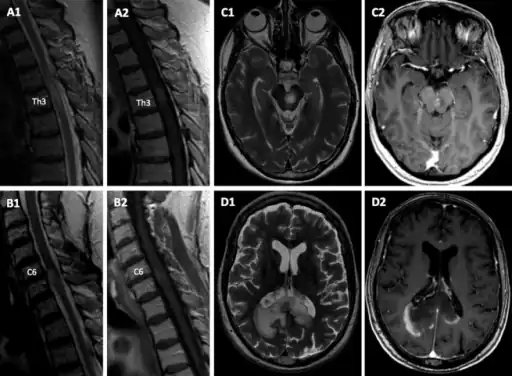

In the young, MRI typically shows ADEM–like lesions and longitudinally extensive transverse myelitis (LETM), whereas optic neuritis and short transverse myelitis are more commonly seen in older patients.[33] However, rare cases of symptomatic MRI-negative MOG-related disease have been described.[34]